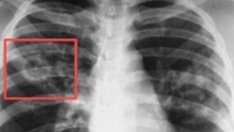

Прегледите са три направления – профилактика на онкологичните заболявания, скрининг на заболяванията на щитовидната жлеза и скрининг на заболяванията на белия дроб.

Скринингът на заболяванията на белия дроб ще се извършват от понеделник до четвъртък включително от 11.00 до 12.00 часа.